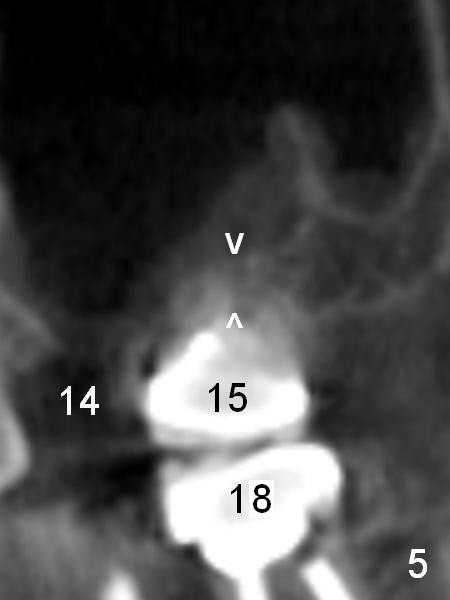

When the implant is placed in the middle of the socket (i.e., septum), it should be shorter (11 mm, Fig.4 coronal section) with sinus lift (bone graft), since the septum height is ~ 2.5 mm (Fig.5 (sagittal section) between arrowheads). The sinus floor dips in between the buccal and palatal roots. Initial osteotomy depth is 2 mm with a trephine bur (smallest). The burs have 2,4,6 mm marks.